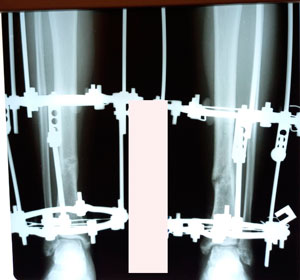

на фиксации

Дата операции - 22.09.2020

Дата снятия аппаратов - 03.02.2021